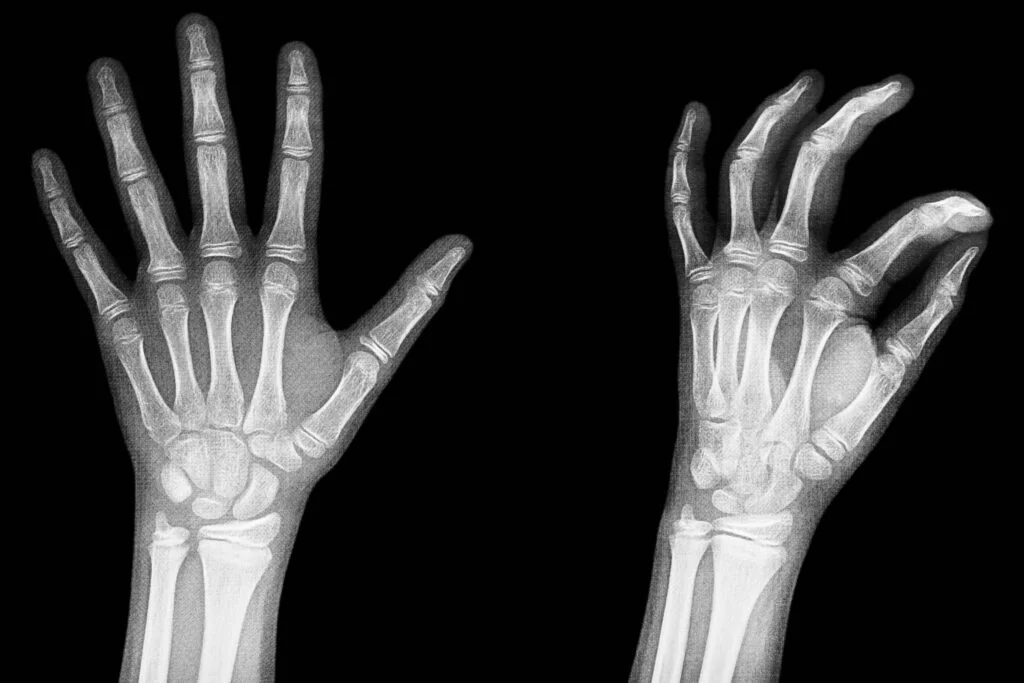

Ο καρπός αποτελείται από οκτώ μικρά οστά που συνδέονται με τα δύο μακριά οστά του αντιβραχίου που ονομάζονται κερκίδα και ωλένη. Το σχήμα των οστών στο χέρι επιτρέπει στον καρπό να λυγίζει και να ισιώνει, να κινείται από τη μία πλευρά στην άλλη και να περιστρέφεται, όπως στην περιστροφή της παλάμης προς τα πάνω και προς τα κάτω.

Οι απλές ακτινογραφίες είναι απαραίτητες για τη διάγνωση των καταγμάτων. Είναι αυτές που θα βοηθήσουν τον γιατρό να αξιολογήσει το είδος του κατάγματος και να λάβει τις αποφάσεις για την οριστική θεραπεία. Μερικές φορές όμως – και ιδίως στα ενδοαρθρικά κατάγματα -είναι απαραίτητη η αξιολόγηση με αξονική τομογραφία, ώστε να απεικονιστεί ο βαθμός της συντριβής του οστού. Ακόμα, η μαγνητική τομογραφία χρειάζεται στις περιπτώσεις όπου υπάρχει υποψία συνδεσμικής βλάβης του καρπού ή στις περιπτώσεις καταγμάτων των μικρών οστών του καρπού, όπως του σκαφοειδούς, που μπορεί να εμφανίσουν άσηπτη νέκρωση.